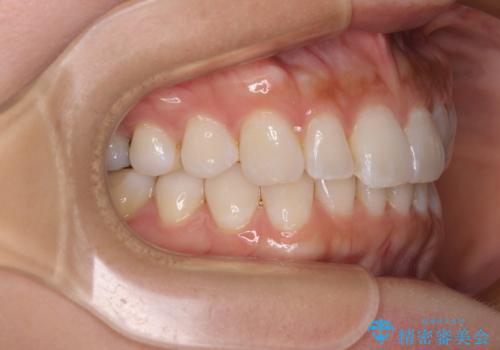

【モニター】前歯のデコボコと小さい前歯 インビザライン矯正とオールセラミッククラウン補綴治療

- 前歯の歯並びと生えてきたときから小さい前歯を気にして来院された患者様です。

上下前歯の歯列不正はインビザラインにより整え、その後に、矮小歯の前歯をオーダーメイドタイプのオールセラミッククラウンにて補綴治療することとしました。

インビザライン矯正の場合、矮小歯を矯正治療後にセラミックとするかどうかを矯正治療開始前に決める必要があるため、悩んでしまう方が多いです。

セラミッククラウンにて大きさを変更することを前提に矯正治療を開始したため、大変満足のいく仕上がりとなりました。